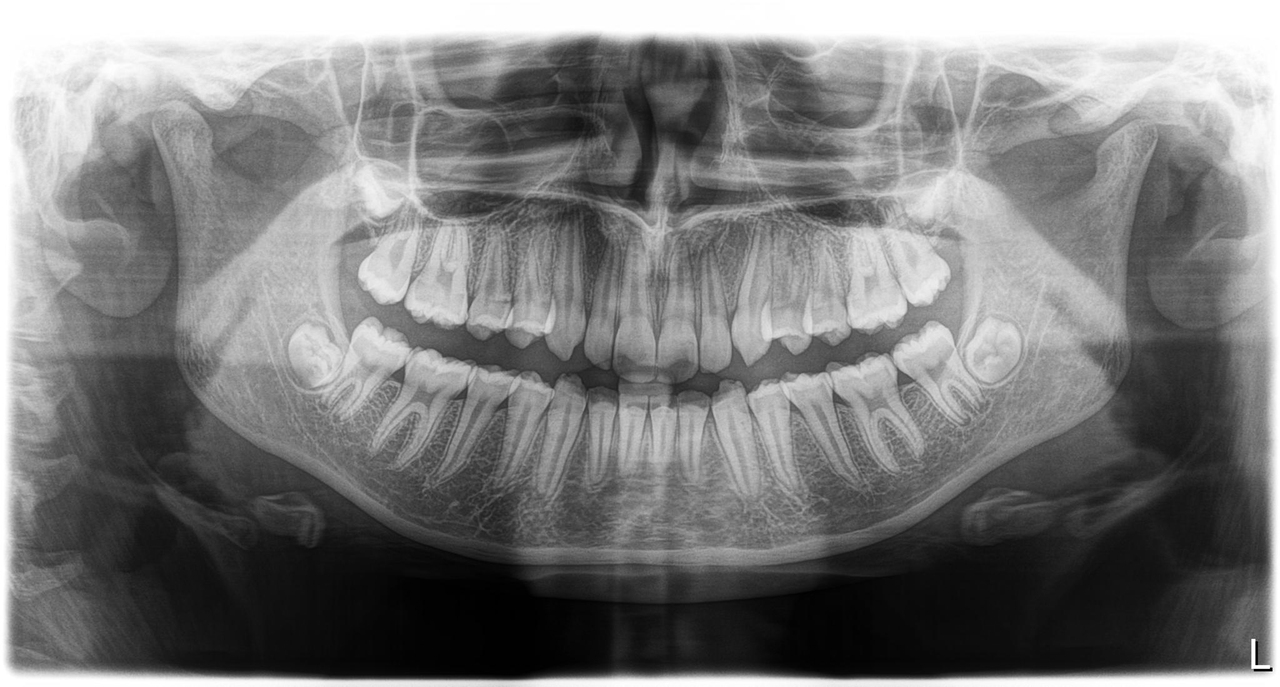

Wisdom Teeth Extractions: Safe and Comfortable Removal

Our oral surgeons specialize in the gentle extraction of wisdom teeth, using advanced techniques to minimize discomfort and promote rapid healing.